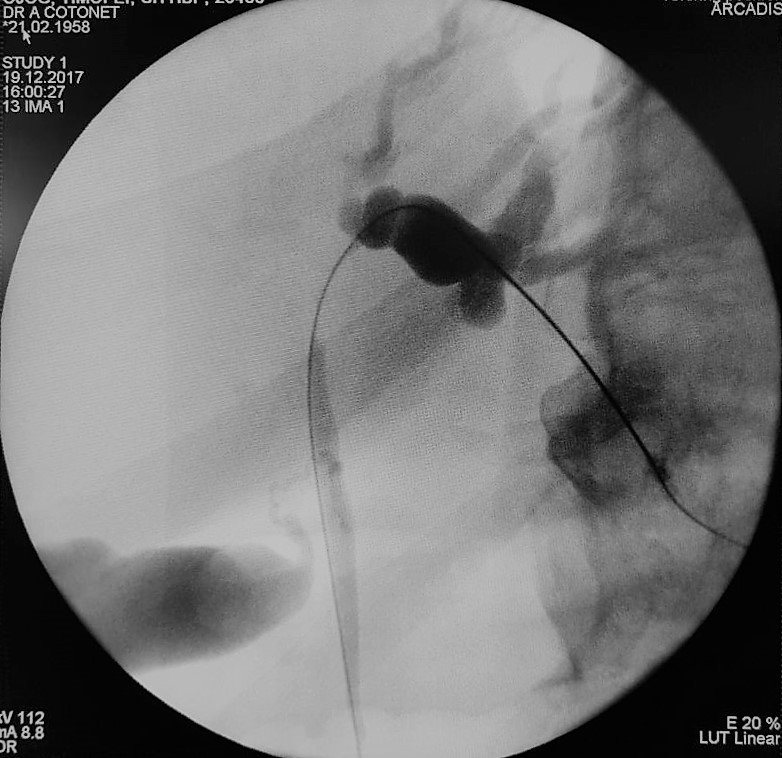

Creşterea siguranţei şi curabilităţii în chirurgia hepatică extensivă a impus dezvoltarea de tehnici, care să asigure funcţionalitatea hepatică a ficatului restant – drenajul biliar preoperatoriu. Scopul drenajului biliar preoperatoriu este de a îmbunătăţi funcţia hepatică şi reduce morbiditatea şi mortalitatea după chirurgie radicală cu hepatectomie majoră, adică rezecţia a mai mult de trei segmente hepatice. Practica arată că rezecţiile hepatice la pacienţii cu icter obstructiv complet şi colangită sunt asociate cu complicaţii severe, dintre care sunt de amintit sângerări intraoperatorii, abcese subfrenice datorate fistulelor biliare şi insuficienţă hepatică. Rolul drenajul percutanat este, pe lângă acela de a obţine o evaluare a extensiei intraductale a carcinomului, cel de a scădea nivelul bilirubinei şi de a permite hipertrofia ficatului dacă se realizează embolizarea venei porte.

Astfel, medicii cabinetului de endochirurgie Cotoneț Alic și Bodrug Roman realizează cu succes acest tip de intervenții deja în mai multe cazuri. Utilajul modern permite cu înaltă precizie puncția ghidată sonografic a căilor biliare urmată la aceeași ședință de drenarea arborelui biliar sub control radiologic.